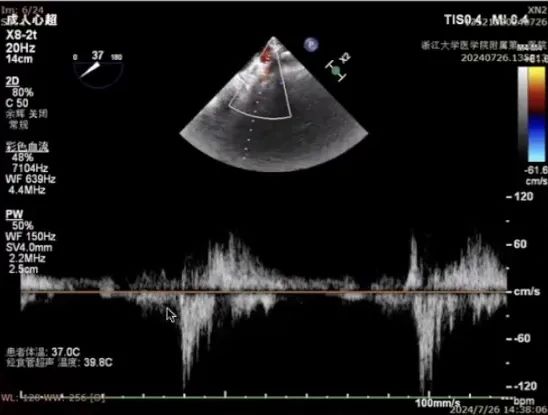

经胸超声评估

经胸超声评估显示,二尖瓣前叶脱垂,并可见广泛反流。

进一步评估患者病变情况,前叶长度2.74mm,后叶长度1.93mm;房间隔前后径4.0cm,房间隔长径6.9cm,瓣口面积6.27cm²,平均跨瓣压差5mmHg。

AML length(A2):2.74mm

PML length(P2):1.93mm

Fail gap:9mm

Fail width:19.2mm

房间隔前后径:4.0cm

房间隔长径:6.9cm

MVA:6.27CM²

PG:5mmHg